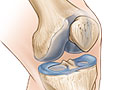

La manera más sencilla de describir la artritis es decir que se trata del desgaste del cartílago de las articulaciones. Este tejido amortiguador es firme, grueso y resbaloso. Cubre y protege el extremo de los huesos, donde se juntan para formar la articulación.

Con la artritis, hay cambios en el cartílago que hacen que este se deteriore. Cuando se deteriora, se genera fricción entre los huesos, lo que causa daño y dolor. Los expertos no saben por qué ocurre ese deterioro en el cartílago. Pero el envejecimiento, las lesiones en las articulaciones, el sobrepeso y la genética podrían ser una parte de la razón.

La osteoartritis se produce cuando los cambios en el cartílago hacen que este se deteriore y se desgaste. Cuando se deteriora el cartílago, se genera fricción entre los huesos, lo que causa daño y dolor. Los expertos no saben por qué sucede esto. Sin embargo, existen factores, como el envejecimiento, la lesión de las articulaciones, el sobrepeso y la genética que podrían aumentar su riesgo.

Qué sucede

La osteoartritis se produce cuando el cartílago que amortigua las articulaciones se deteriora y se desgasta. Cuando esto sucede, se genera fricción entre los huesos, lo que causa daño y dolor. En la mayoría de los casos, lleva años que el cartílago se deteriore.